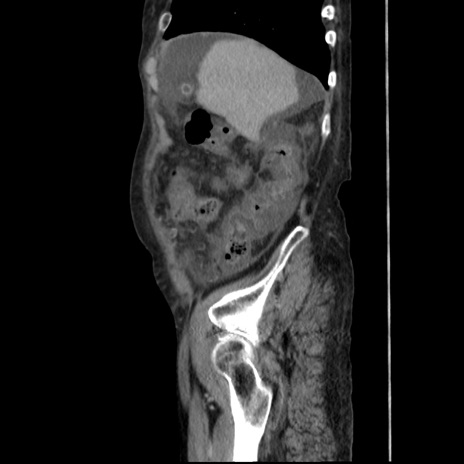

冠状断像

【症例】80歳代 女性

【主訴】腹部膨満感

【現病歴】他院にて肝硬変にてフォロー中。1週間前から便秘、腹部膨満感、臍部腫瘤あり受診となる。

【既往歴】肝硬変

【身体所見】腹部膨隆あり、皮膚変化なし、疼痛なし。

【データ】WBC 4600、CRP 0.25